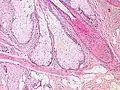

Al microscopio electrónico se observa que las células periféricas glandulares contienen tonofilamentos, reflejando su origen epidérmico, y escasos lípidos. A medida que los lípidos se forman, el glucógeno se va consumiendo, los tonofilamentos se van desplazando y el citoplasma se rellena de vacuolas. En la célula las vacuolas se fusionan entre sí provocando un aumento de tamaño hasta cien veces el normal, adquiriendo un aspecto de célula de cuerpo extraño. En un estadio posterior se desorganiza la membrana y la célula se rompe eliminando su contenido al canal sebáceo.